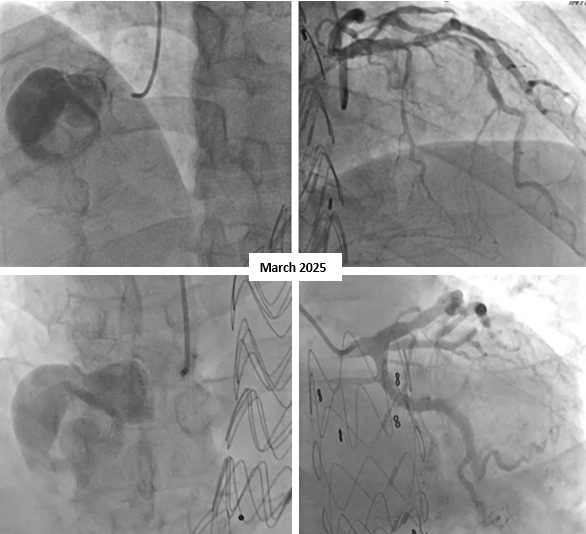

The coronary angiography showed a giant right coronary artery (RCA) aneurysm with total occlusion at mid-RCA and collateral flow from the left circumflex artery. It is different with right coronary angiography at 4 years ago that showed no coronary aneurysm. The left coronary artery has a good flow to the distal without any significant stenosis and patent stent on 1st diagonal artery branch.

After discussing with the heart team, the surgery was planned. After several days of patient's condition improvement, the surgical was performed. Surgical exploration was undertaken via median sternotomy. Intraoperative findings included a giant RCA aneurysm measuring approximately 6 cm with massive intramural haematoma, a fistulous connection to the RA, and a proximally visible RCA orifice with distal total occlusion. The aneurysmal sac was resected, the RA wall was repaired, and a coronary artery bypass graft (CABG) was performed using a reversed saphenous vein graft from the proximal RCA to the distal RCA segment. Echocardiography on 4th day postoperative day (POD 4) showed preserved biventricular function without residual mass. Coronary CT angiography on POD 7 confirmed patent RCA graft and resolution of the aneurysmal mass.